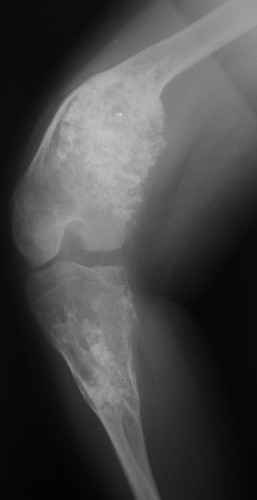

Диагноз: Дисхондроплазия. Варусная деформация дистального метафиза правой бедренной кости; состояние после оперативных вмешательств (1993 и1994 гг.).

Деформация правой нижней конечности с 6 месяцев (стала прогрессировать после года, с момента начала ходьбы). Поставлен диагноз болезнь Олье, варусная деформация, укорочение правой нижней конечности на 4,5 см. 1993 г. - операция остеоклазия на уровне очагов поражения в н/3 правой бедренной кости и в/3 правой большеберцовой кости с одномоментной коррекцией деформации и фиксацией костных фрагментов спицами Киршнера.После начала статической нагрузки (1994 г.) появился рецидив деформации и укорочения. Вторая операция - ЧКО АВФ, аппарат демонтирован через 2недели в связи с развившимся на уровне стержня переломом, после чего находилась в гипсовой повязке до консолидации костных фрагментов. Далеелечилась консервативно в гипсовой повязке. Выраженная деформация и укорочение правой нижней конечности. Относительная длина бедер: справа -34 см, слева - 51 см; анатомическая длина голеней: справа - 29 см, слева - 39 см. Величина варусной деформации на уровне дистального отдела правого бедра составляет - 80 град. Амплитуда движений в коленных суставах (разгибание/сгибание ): справа - 0/0/100 град.; слева - 0/0/30 град. Отмечается боковая и ротационная нестабильность на уровне правого коленного сустава. Амплитуда движений в голеностопных суставах - в норме. Тактика лечения? Заранее благодарю! С уважением,А.В.Владзимирский

Высылаю вам фото подобной больной, у нее тоже первая попытка до меня была безуспешной.

Нужен аппарат Илизарова стабильный с множеством спиц с напайкой, временной фиксацией колена аппаратом на голени. Наверное, проще первый раз начать с бедра, остеотомию выполнить прямо на уровне перехода очага в дистальный метафиз бедра. Дистракционный остеогенез вызовет перестройку хрящевой ткани в костную. Понадобится еще пара этапов.